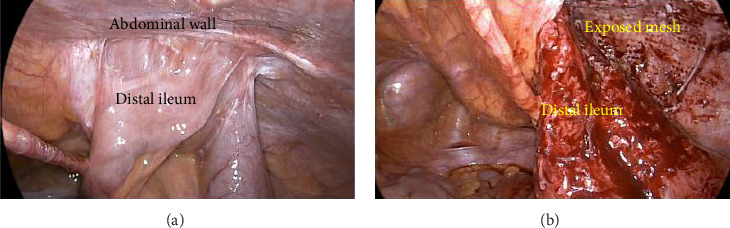

The objectives were to highlight that: (1) mesh erosion related partial small bowel obstruction after laparoscopic totally extraperitoneal (TEP) inguinal hernia repair (IHR) as an uncommon complication can clinically and radiologically mimic ileocolic Crohn's disease in young adults; and (2) implore clinicians to consider a broad set of differential diagnosis and prompt involvement of other subspecialties, especially if preliminary investigations and treatment yield minimal results. The authors report a 34-year-old male who presented with computed tomography (CT) findings of ileitis, which was initially investigated for Crohns' disease. Due to persisting abdominal pain and negative initial investigations, he underwent a laparotomy demonstrating secondary mesh migration with erosion into distal ileum requiring bowel resection, 2.5 years after an uneventful laparoscopic right TEP IHR. The patient made an uneventful postoperative recovery and at 6 weeks follow-up, he had resolution of abdominal pains, and normal bowel function.